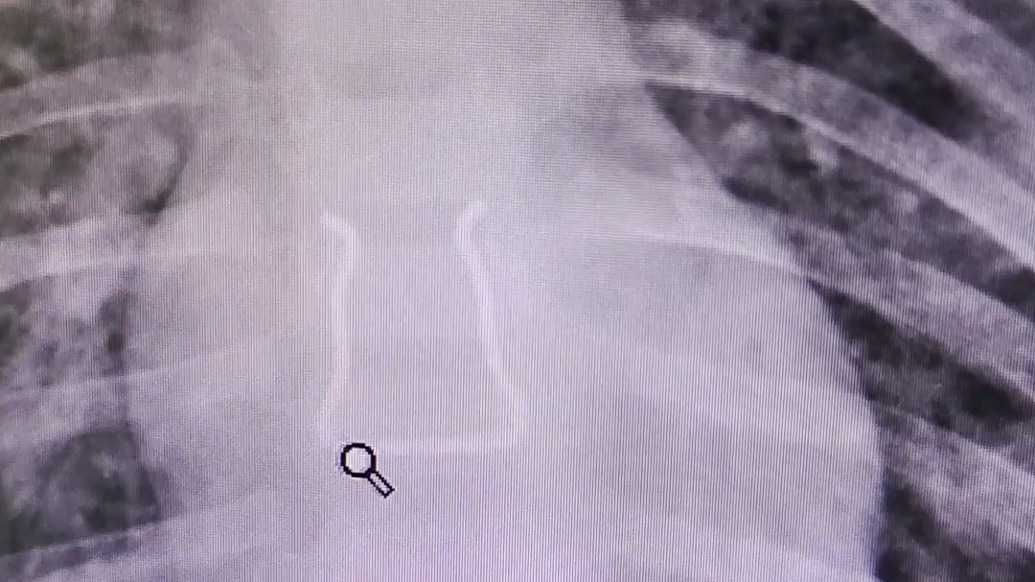

近日,廣東深圳。一名幼童誤吞“Ω”形金屬鉤,家長(zhǎng)用海姆立克法催吐無(wú)果后送醫(yī)。醫(yī)生稱(chēng)該金屬鉤若由食道取出,或刺破心臟附近的血管,為規(guī)避大出血風(fēng)險(xiǎn),醫(yī)生將異物推至胃腸,最終異物順利排出。幼童目前痊愈出院。